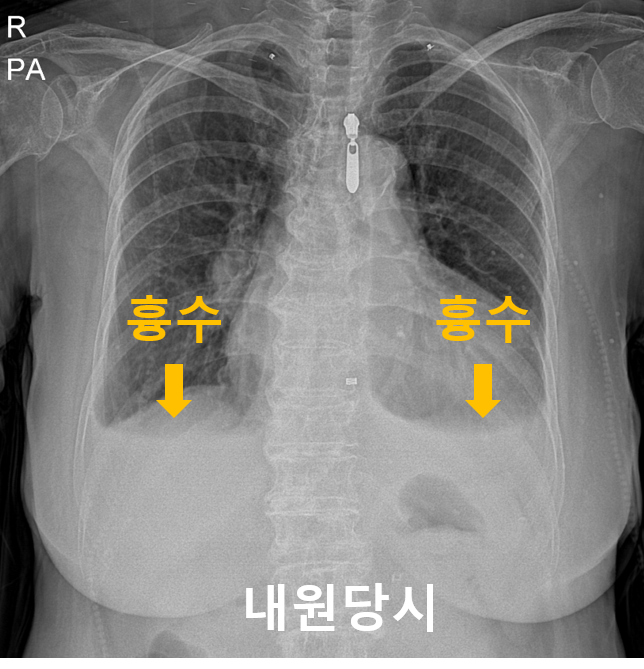

89세 여환이 호흡곤란을 주소로 내원하였습니다.

흉부엑스레이를 찍어보았더나 심장비대와 함께 양쪽폐에 흉수가 차있었습니다.

이는 심부전에의한 증상으로 간주하고 이뇨제를 투여하였습니다.